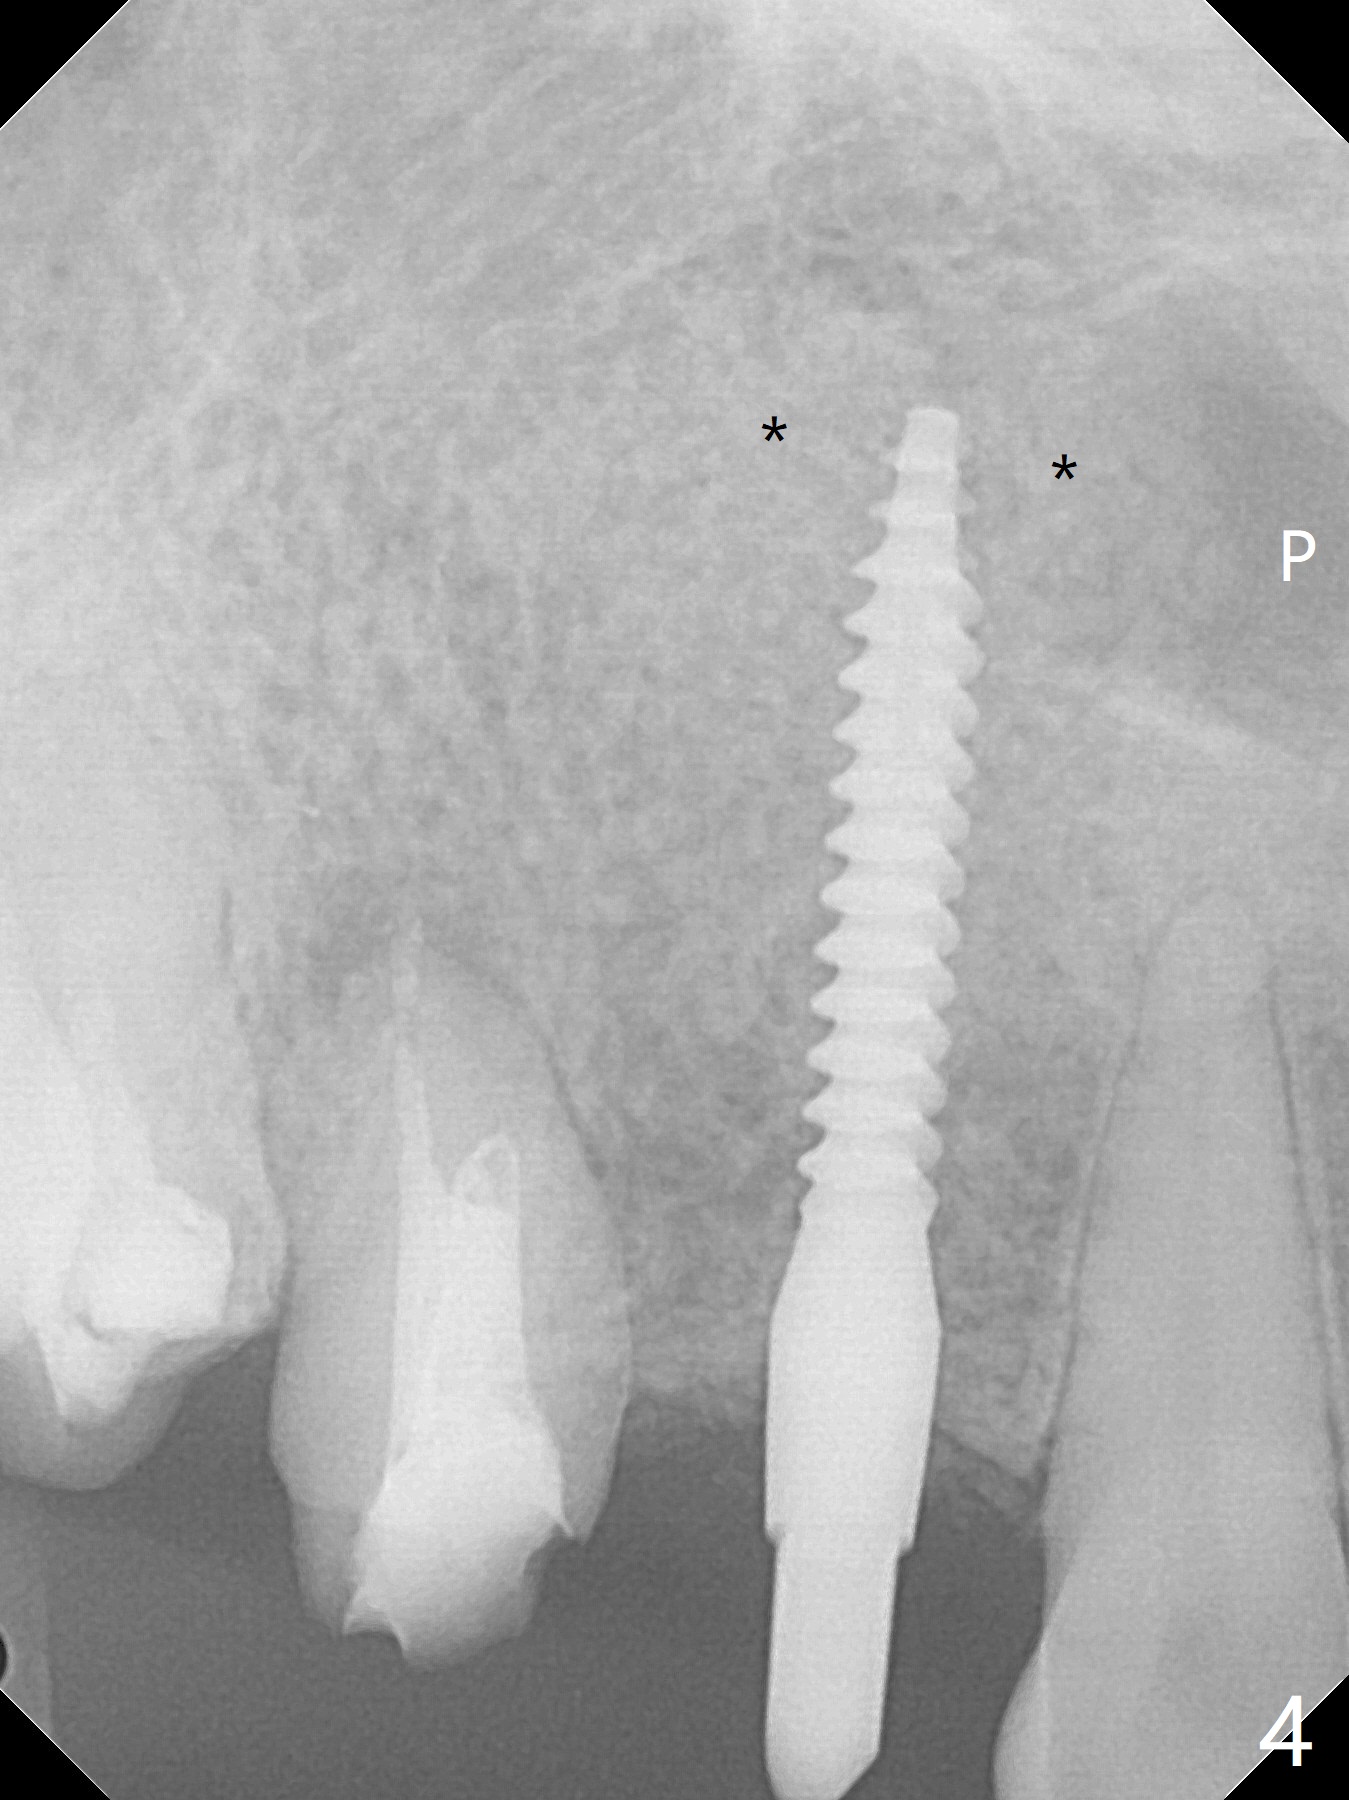

Osteotomy starts with guide and 2.2 mm drill for initial 3.5 mm palatal. A semilunar incision is made buccal to remove the impacted canine (#6 by sectioning). With direct vision buccal and palatal, the final osteotomy is finished free hand with 1.2 and 1.5 mm drills. Initially buccal perforation occurs, the osteotomy route is corrected later (Fig.1). When a 2.5x15 mm 1-piece implant is being placed, it perforates into the buccal concavity again. After redirection, the trajectory seems to be acceptable (Fig.2: CT coronal section). Three coronal implant threads are exposed partially palatal (Fig.3: CT 3-D palatal view). The implant is then turned 2-3 times with insertion torque reaching 40 Ncm. The incision is closed with suture following Osteogen plug placed in the most coronal portion of the socket (Fig.4 P) and allograft (*) in the remaining socket around the apical portion of the implant as well as palatal. The incision does not heal 1 month postop (Fig.5). PRF membrane will be placed next visit. Next visit the wound in fact is healing (Fig.6). PRF is unnecessary. The patient will return for impression 3 months postop. To be cosmetically pleasing, prepare local anesthetic and Laser for gingivectomy (Fig.7 red curved line). There is no bone loss around the implant 3.5 months postop (Fig.8). With topical, minor gingivectomy with laser creates papillae mesial and distal to the implant (Fig.9, 10 (incisal view)). After reline, there is appearance of a canine (Fig.11). The patient returns for impression 5 months postop; there is bone around the apex of the implant (Fig.12 *). The hard and soft tissues remain healthy when final restoration is delivered (Fig.13,14). The buccal plate reforms and #6 socket heals 12 months postop (6 months post cementation, Fig.15). The gingiva remains healthy at #4-6 nearly 2 years post cementation (Fig.16).